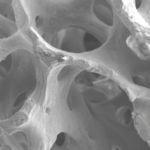

Superior initial stability makes a perfect match for GBR using i-Gen membrane

AnyRidge can be placed in any ridge thanks to its knife thread. AnyRidge Knife thread has perfect stability in Regenerated bone.